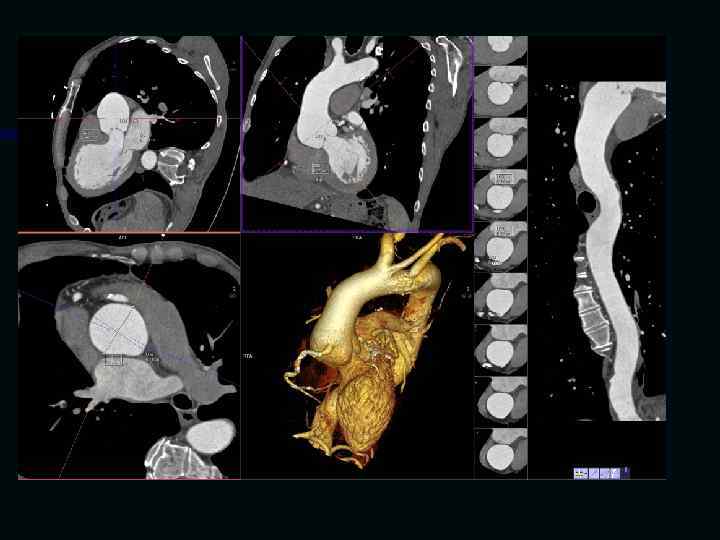

Исследование сосудов грудной клетки

Исследование сосудов брюшной полости